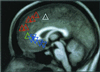

Medial prefrontal cortex (MPFC) is among those brain regions having the highest baseline metabolic activity at rest and one that exhibits decreases from this baseline across a wide variety of goal-directed behaviors in functional imaging studies. This high metabolic rate and this behavior suggest the existence of an organized mode of default brain function, elements of which may be either attenuated or enhanced. Extant data suggest that these MPFC regions may contribute to the neural instantiation of aspects of the multifaceted "self." We explore this important concept by targeting and manipulating elements of MPFC default state activity. In this functional magnetic resonance imaging (fMRI) study, subjects made two judgments, one self-referential, the other not, in response to affectively normed pictures: pleasant vs. unpleasant (an internally cued condition, ICC) and indoors vs. outdoors (an externally cued condition, ECC). The ICC was preferentially associated with activity increases along the dorsal MPFC. These increases were accompanied by decreases in both active task conditions in ventral MPFC. These results support the view that dorsal and ventral MPFC are differentially influenced by attentiondemanding tasks and explicitly self-referential tasks. The presence of self-referential mental activity appears to be associated with increases from the baseline in dorsal MPFC. Reductions in ventral MPFC occurred consistent with the fact that attention-demanding tasks attenuate emotional processing. We posit that both self-referential mental activity and emotional processing represent elements of the default state as represented by activity in MPFC. We suggest that a useful way to explore the neurobiology of the self is to explore the nature of default state activity.